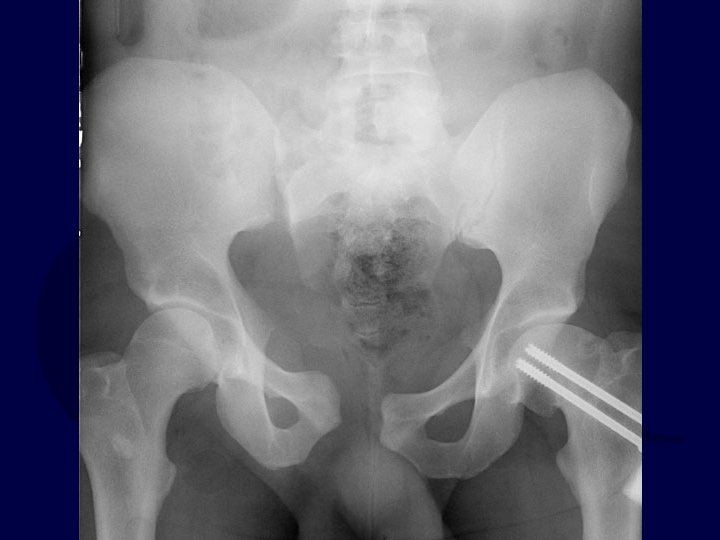

Radiographic Signs of Instability • Sacroiliac displacement of 5 mm in any plane • Posterior fracture gap (rather than impaction) • Avulsion of fifth lumbar transverse process, lateral border of sacrum (sacrotuberous ligament), or ischial spine (sacrospinous ligament)

Pelvic Fractures & Hemorrhage • Fracture pattern associated with risk of vascular injury (Young & Burgess) • External rotation and vertical shear injury patterns at higher risk for a vascular injury that internal rotation patterns • APC & VS (antero-posterior compression and vertical shear) at increased risk of hemorrhage • Injury patterns that are tensile to N-V structures at increased risk • (eg iliac wing fractures with GSN extension Dalal et al, JT, 1989 Burgess et al, JT, 1990 Whitbeck et al, JOT, 1997 Switzer et al, JOT, 2000 Eastridge et al, JT, 2002

Pelvic Fractures & Hemorrhage: Young and Burgess Classification Lateral Compression (LC) Anteroposterior Compression (APC) ER & VS > IR APC & VS at increased risk Vertical Shear (VS)